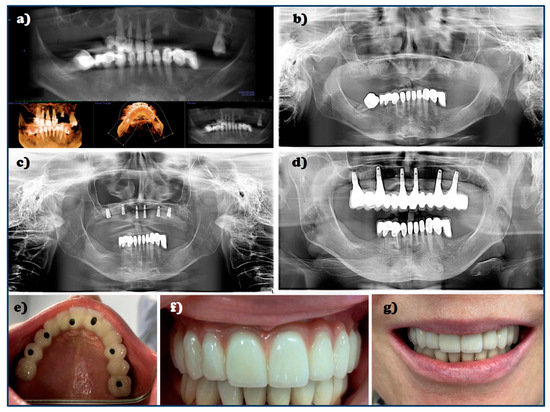

- Dobrzański, L.B.; Achtelik-Franczak, A.; Dobrzańska, J.; Dobrzański, L.A. The digitisation for the immediate dental implantation of incisors with immediate individual prosthetic restoration. JAMME 2019, 97, 57–68. [Google Scholar] [CrossRef]